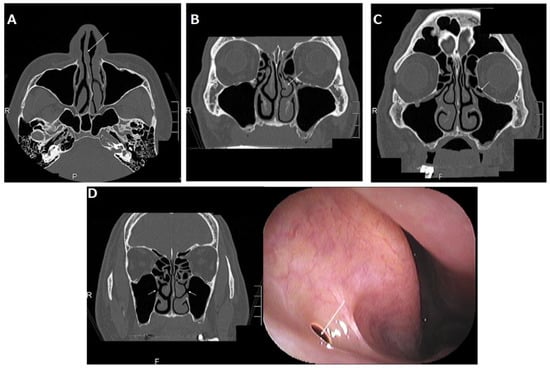

3. Common Maxillary Sinus Pathologies before Maxillary Implantation

The common maxillary sinus pathologies that can be identified on coronal CT images of the paranasal sinus at our institution are shown in Figure 5. These pathologies are classified into three pathologies: those that need treatment, those that do not need treatment, and those that are not candidates for maxillary implantation. A normal maxillary sinus, retention cyst or solitary polyp, and mucosal thickening in the maxillary sinus do not need treatment before maxillary implantation (Figure 5A–C), whereas preoperative sinusitis needs treatment because it is a cause of the development of postoperative maxillary sinusitis (Figure 5D–F) [17]. Patients with a postoperative maxillary cyst also need treatment (Figure 5G). Patients with eosinophilic chronic rhinosinusitis are not suitable for maxillary implantation (Figure 5H).

3.1. Retention Cyst or Solitary Polyp

A retention cyst is described as one of the most common pathological findings of the maxillary sinus and usually presents as a dome-shaped radiopaque soft-tissue mass attached to the bony walls of the sinus (Figure 5B). Retention cysts are benign lesions that can originate from the accumulation of fluids inside the sinus membrane, which result from a ductal obstruction of the seromucous glands [18]. When patients with a small retention cyst or polyp have no complaints, ENT treatments are not required. Furthermore, the placement of dental implants after a sinus lift in patients with retention cysts is safe and presents a high chance of survival, regardless of whether the lesion is removed [19]. Therefore, we think that patients with a small cyst or solitary polyp in the maxillary sinus can still receive a maxillary implant with or without a sinus lift.

3.2. Mucosal Thickening in the Maxillary Sinus

Patients with mucosal thickening that is less than one-third to one-half of the maxillary sinus height and localized to the lesion around the teeth (Figure 5C) can still receive a maxillary implant with or without a sinus lift [20,21].

3.3. Acute Rhinosinusitis

Rhinosinusitis is defined as inflammation of one or more paranasal sinuses; acute rhinosinusitis is defined by symptoms such as nasal congestion, rhinorrhea, facial pain, hyposmia, and sneezing, which last less than 12 weeks [22]. Imaging often indicates air-fluid levels or fluid accumulation (Figure 5D). After the possibility of coronavirus disease 2019 (COVID-19) is ruled out by a severe acute respiratory syndrome coronavirus 2 (SARS-CoV-2) RT-PCR test—because the clinical manifestations of rhinosinusitis are similar to the symptoms of COVID-19 [23] and patients recover from the illness by conservative ENT treatment—they can still receive a maxillary implant with or without a sinus lift.

3.4. Chronic Rhinosinusitis

Chronic rhinosinusitis is defined as symptoms that last more than 12 weeks [22]. Chronic rhinosinusitis is classified into two categories: neutrophilic and eosinophilic. Furthermore, neutrophilic chronic sinusitis has two patterns: with or without a benign tumor.

3.4.1. Neutrophilic Chronic Rhinosinusitis

CT often shows almost all opacification of the maxillary sinus or other paranasal sinuses (Figure 5E). After conservative and/or surgical treatment by FESS, patients can still receive an implant treatment with or without a sinus lift [24].

3.4.2. Neutrophilic Chronic Rhinosinusitis with a Benign Tumor Such as Osteoma

Neutrophilic chronic rhinosinusitis with a benign tumor in the paranasal sinuses is a subtype of neutrophilic chronic sinusitis (Figure 5F). This disease can be considered to result from the obstruction of the natural ostium of the maxillary sinus by the tumor. The surgical options for this disease are an endoscopic procedure or a combined external and endoscopic procedure [25]. If a surgeon selects the former and can achieve complete resection, patients can still receive a maxillary implant with or without a sinus lift. Otherwise, when a surgeon selects the combined approach, dentists should consider the possibility of a postoperative maxillary cyst (POMC) at the time of the maxillary implant.

3.4.3. Eosinophilic Chronic Rhinosinusitis (ECRS)

ECRS is recognized as refractory chronic rhinosinusitis despite the combination of macrolide therapy and FESS, which is effective for neutrophilic chronic rhinosinusitis [26]. ECRS has a strong tendency for recurrence after FESS. CT scan images of ECRS patients show them to be ethmoid-sinus-dominant (Figure 5H), while CT of neutrophilic chronic sinusitis shows maxillary predominance in the early stages. Patients with ECRS tend to be more likely to develop rhinosinusitis symptoms after maxillary implant treatment, so they are not suitable for implant treatment or other prostheses such as dentures; implant-supported overdentures are recommended as an alternative method to avoid maxillary implant treatment [27].

3.5. POMC

POMC is a delayed complication of maxillary sinus surgery, such as Caldwell–Luc surgery, which is a radical technique used to remove infection and diseased mucosa from the maxillary sinus (Figure 5G). Marsupialization with drainage of a POMC should be performed before the insertion of an implant, in order to prevent implant failure resulting from possible bone destruction around the dental implant following the expansion of the POMC [28].

Figure 5. (A) Almost normal maxillary sinus and left concha bullosa of the middle turbinate (arrow); (B) retention cyst or solitary polyp in the right maxillary sinus (arrow); (C) mucosal thickening in the left maxillary sinus (arrow); (D) air-fluid level or fluid accumulation in the left maxillary sinus (most often indicating acute rhinosinusitis) (arrow); (E) total opacification of the maxillary sinus or other paranasal sinuses (most often indicating chronic rhinosinusitis) (arrow); (F) left chronic sinusitis with ethmoidal osteoma (arrow); (G) right two postoperative maxillary cysts (POMC) (arrow); (H) eosinophilic chronic rhinosinusitis (arrow).